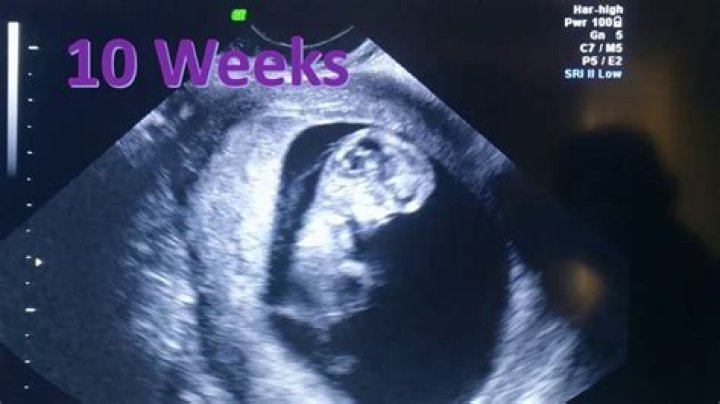

Can the baby move at 10 weeks?

10 Weeks Pregnant: Your Baby's Development Although you won't be feeling any movement yet, if you were to have an ultrasound scan at 10 weeks p...